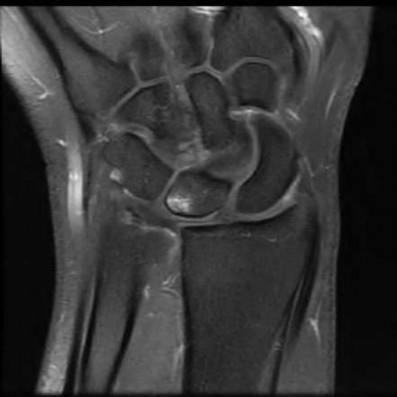

Question 6:

A 22-year-old male falls onto an outstretched hand and sustains a displaced fracture through the proximal pole of the scaphoid. Avascular necrosis of the proximal pole is highly likely due to the disruption of its primary vascular supply. Which vessel provides this critical retrograde perfusion?

Correct Answer: Dorsal carpal branch of the radial artery

Explanation:

The primary blood supply to the scaphoid is from the dorsal carpal branch of the radial artery, which enters the dorsal ridge of the scaphoid at the waist and courses proximally. This retrograde blood flow makes proximal pole fractures highly susceptible to avascular necrosis and nonunion. The superficial palmar branch provides a minor supply (about 20%) to the distal pole.